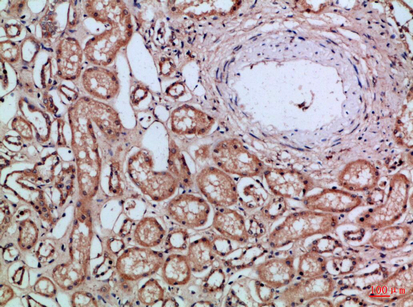

Immunohistochemistry analysis of paraffin-embedded Human kidney using CD66a/b/c antibody.High-pressure and temperature Sodium Citrate pH 6.0 was used for antigen retrieval. |